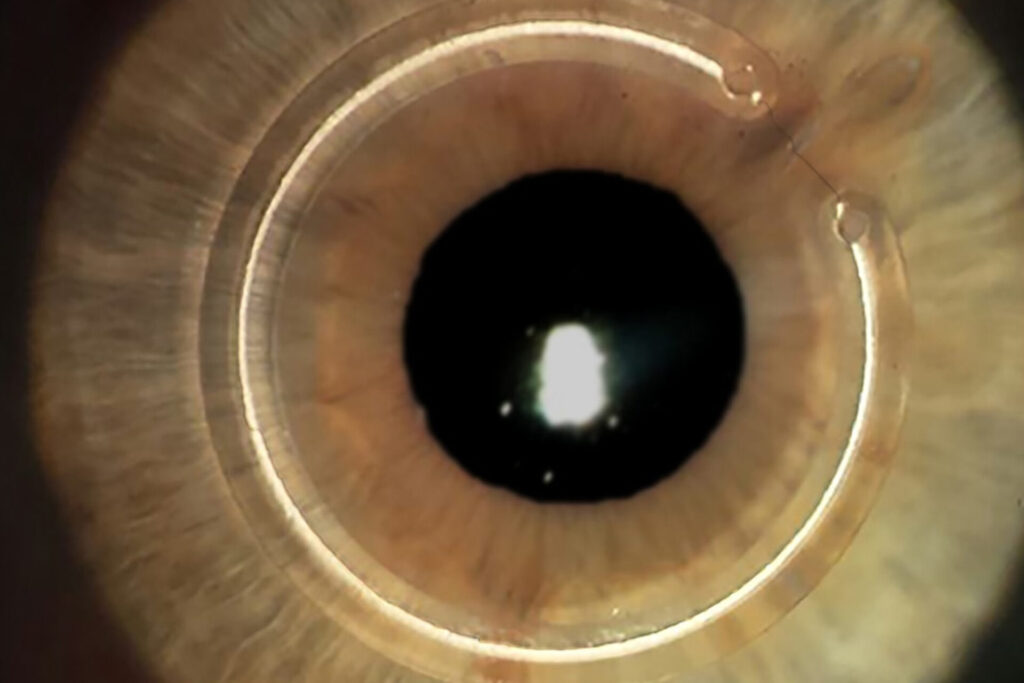

Usado para reabilitar a visão. Consiste no implante de pequenos segmentos de acrílico na espessura da córnea. Estes anéis ajudam a regularizar a curvatura, tornando a córnea mais plana. O resultado é uma melhora significativa da visão e uma melhor adaptação às lentes de contacto ou óculos.